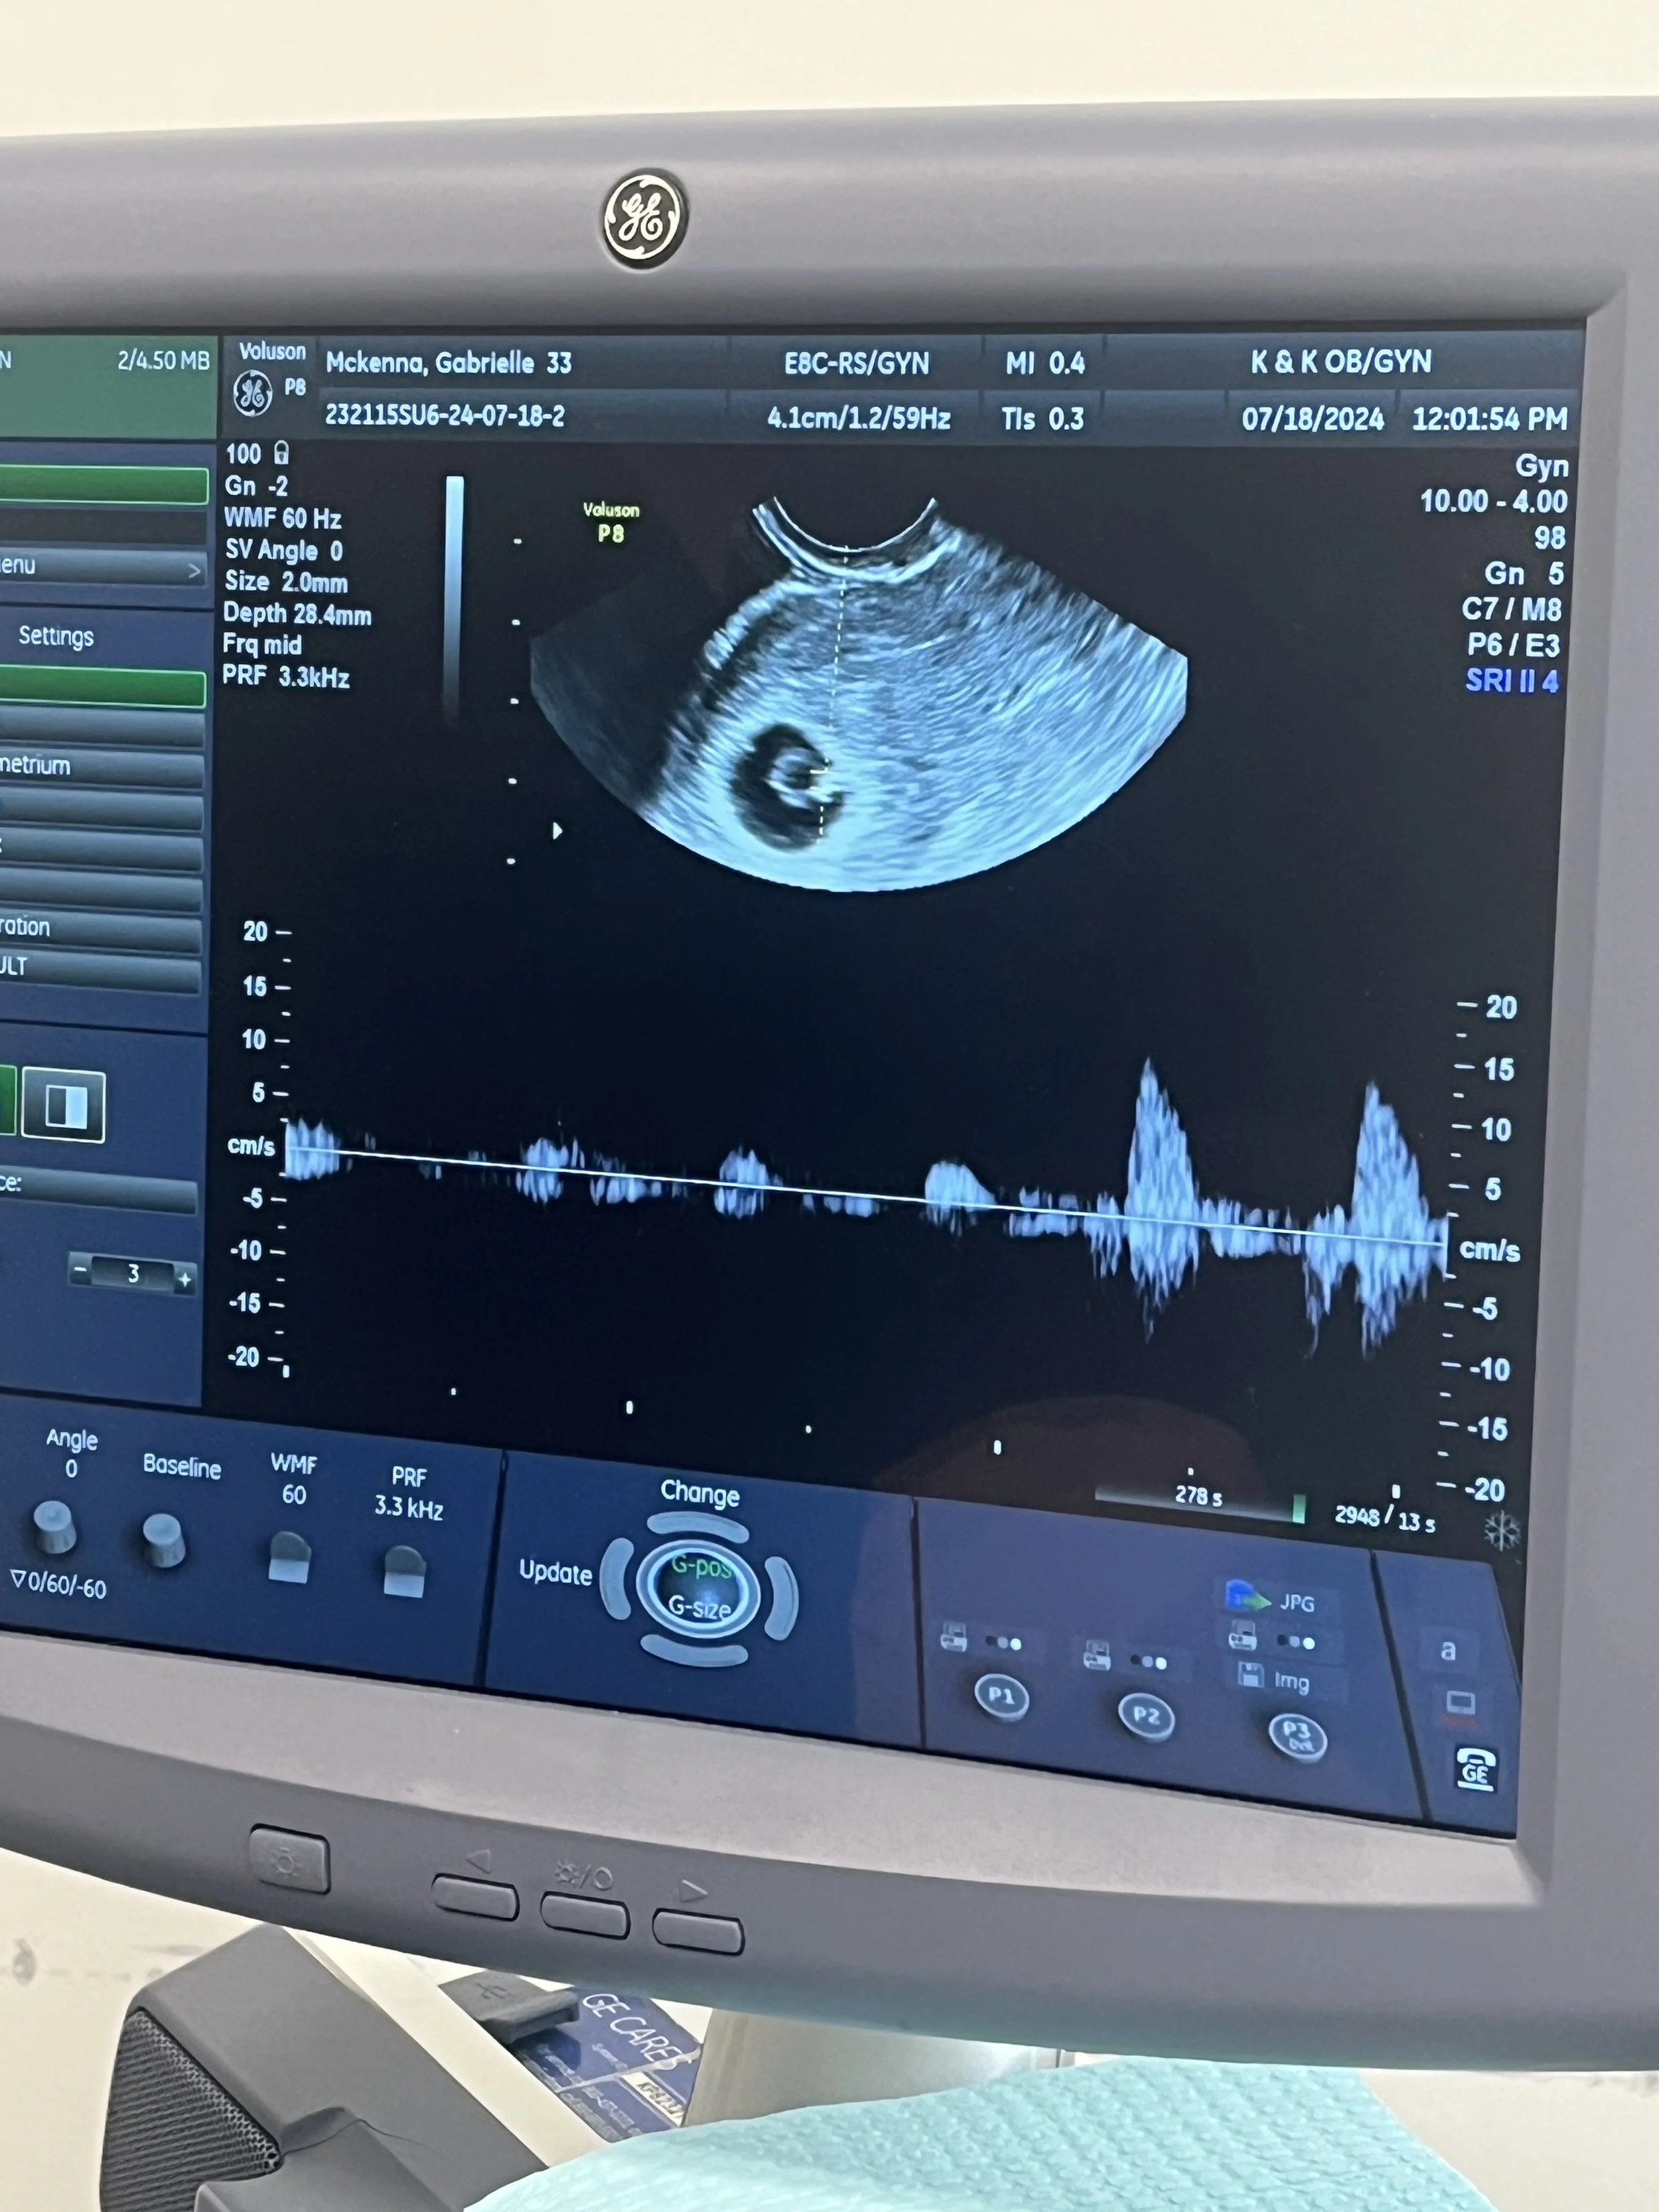

A doctor confirmed the pregnancy, and provided us with a due date: February 28th, 2025. In an ultrasound, we heard the baby’s heartbeat. We made plans for the future, like searching for houses with a nursery in mind, and we were so excited to find out the gender soon.

We had been through multiple ultrasounds already, and had already heard the baby’s heartbeat. But I was anxious, because I had been bleeding. Despite the scans we had, and that the baby showed signs of growth, our due date kept getting pushed back. We were told the baby was tracking for delivery March 8th. At every appointment I held my breath as I watched the screen.

I remember the doctor knocking on the door, entering the room, and warmly saying “are you ready to see your little peanut?” before beginning the exam. The little shape of a fetus was there on screen when we began, but it looked so small. The doctor kept moving the monitor in silence. The seconds that passed felt like hours… and suddenly I was filled with dread. I imagined her saying the words before she said them.. “I’m not finding a heartbeat, I’m so sorry.”

At our 8 week appointment I returned for another ultrasound, this time to hear the baby’s heartbeat. It was a critical moment. The Doctor didn’t waste time, knowing I was anxious as I was gripping Ryan’s hand. Moments later we heard our baby’s heartbeat for the first time. It was the most beautiful sound in the world. Strong and fast, and powering this little tiny life. The baby was starting to take shape.